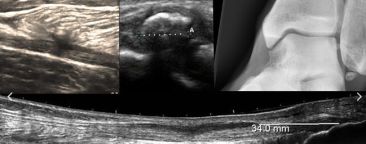

- The advantages and disadvantages of using ultrasound in MSK clinics..what can and can’t you visualise with ultrasound?

- The role of ultrasound in guided peripheral joint injections